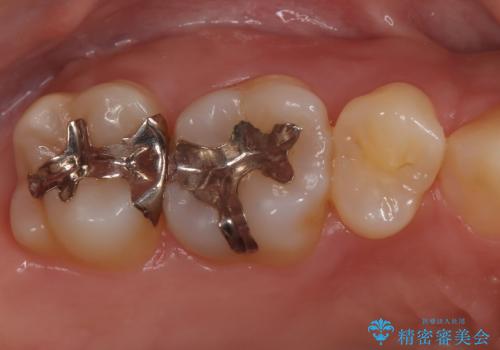

- 金属を外してセラミックを入れたいことを主訴に来院された患者さんです。

セラミックインレーにて修復を行いました。